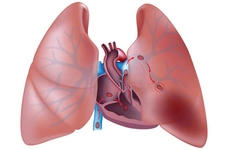

Akciğer tansiyonu, yani pulmoner hipertansiyon, akciğerlerdeki kan damarlarındaki basıncın artması durumudur. Bu rahatsızlık, kalp ve akciğer fonksiyonlarını olumsuz etkileyebilir. Belirtileri arasında nefes darlığı ve yorgunluk bulunurken, tedavi yöntemleri hastalığın nedenine göre değişir. Erken tanı ve müdahale hayati önem taşır.

Akciğer tansiyonu, pulmoner hipertansiyon olarak da bilinen bu durum, akciğerlerdeki kan damarlarının basıncının normalden daha yüksek olması anlamına gelir. Bu rahatsızlık, kalp ve akciğer fonksiyonlarını etkileyebilir ve ciddi sağlık sorunlarına yol açabilir. Bu makalede, akciğer tansiyonunun insan sağlığı üzerindeki etkileri, belirtileri, nedenleri ve tedavi yöntemleri detaylı bir şekilde ele alınacaktır. Akciğer Tansiyonu Nedir?Akciğer tansiyonu, akciğerlerdeki kan damarlarındaki basıncın yükselmesi sonucu ortaya çıkar. Normalde, akciğerlerdeki kan damarlarının basıncı 8-20 mmHg arasında olmalıdır. Ancak bu değerlerin üzerinde bir ölçüm, pulmoner hipertansiyon olarak kabul edilir. Akciğer tansiyonu genellikle, kalp sağlığı üzerinde de olumsuz etkiler yaratır. Akciğer Tansiyonunun BelirtileriAkciğer tansiyonu, birçok belirti ile kendini gösterebilir. Bu belirtiler, hastalığın şiddetine göre değişiklik gösterebilir. Yaygın belirtiler şunlardır: